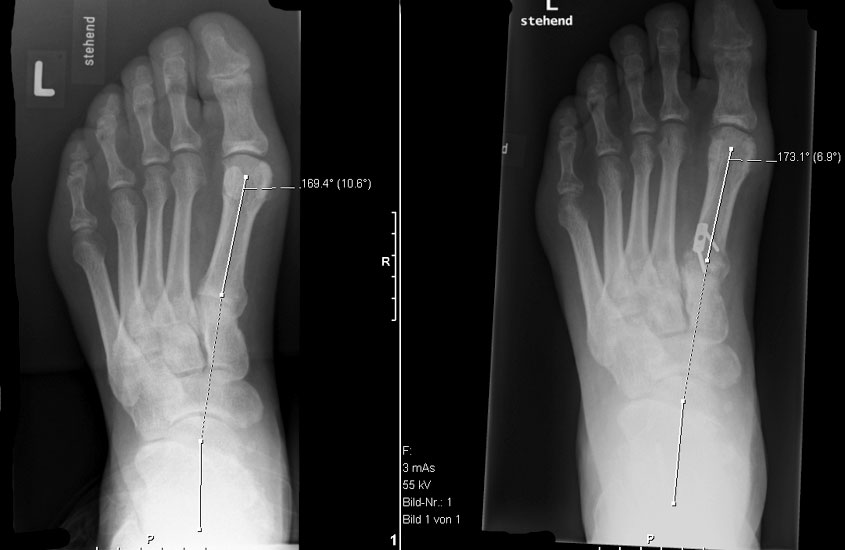

Dorsalflektierende Osteotomien des medialen Mittelfuβes (Abb. 6 – 9, Video 4)

• Erhöhter lateraler Talo-Metatarsale I Winkel (Meary-Winkel) als Ausdruck des plantarflektierten medialen Mittelfuβes, insbesondere im "forefoot driven hindfoot varus" (positiver Coleman block Test).

Generell wird die dorsalflektierende MT I Osteotomie (Abb. 6 und 7) nicht isoliert ausgeführt, sondern ist Teil der gesamten Hohlfuβ-Korrektur. Beim absolut flexiblen Hohlfuβ ist sie gelegentlich zusammen mit einem Peroneus longus auf brevis oder einem Release der Plantarfaszie ausreichend. Diese Osteotomie ist einfach durchzuführen und hat eine geringe Pseudarthroserate.

Eine ähnliche dorsalflektierende Osteotomie des Os cuneiforme mediale (reversed Cotton Osteotomie, Abb. 8 und 9), ebenfalls mit Entnahme eines dorsal basierten Knochenkeils, ist effektiver im Ausmass der Korrektur, jedoch oftmals wegen der Insertion des kräftigen Lisfranc-Ligaments nur schwierig zu schliessen.